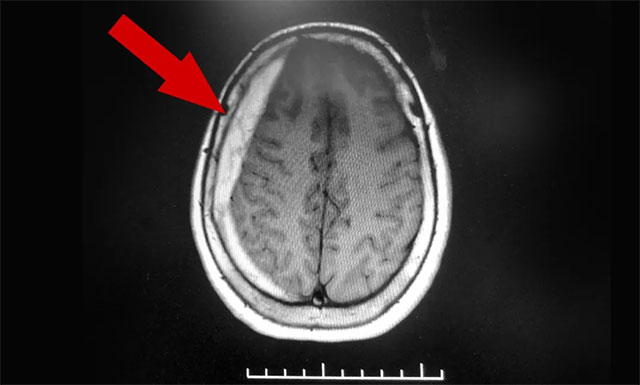

今年6月,82歲的金阿婆(化名)因腦梗至上海某醫(yī)院救治,所幸沒有大礙。然而到了9月份,金阿婆感到持續(xù)性頭痛發(fā)作,且有不斷加重的趨勢(shì)。她以為腦梗又犯了,便慕名來到上海藍(lán)十字腦科醫(yī)院尋求進(jìn)一步治療。醫(yī)院神經(jīng)內(nèi)科專家李淑琴醫(yī)生在門診為金阿婆完善相關(guān)影像學(xué)檢查后發(fā)現(xiàn),患者右側(cè)額顳部顱骨內(nèi)板下方呈新月形高密度影,是硬膜下血腫的典型影像表現(xiàn)。

▲ 患者右側(cè)額顳部顱骨內(nèi)板下方呈新月形高密度影